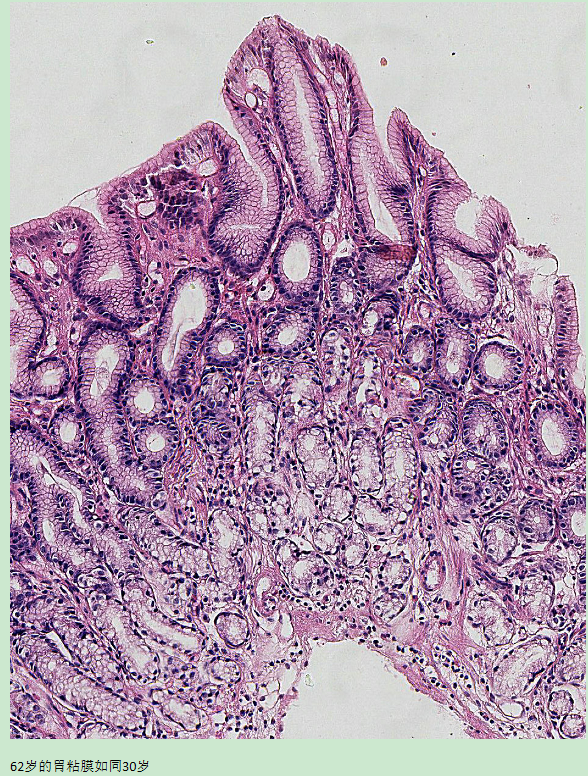

当我们在深入观察人体的胃部(胃镜+病理)后,一定会发现胃龄在不断变化之中。有的人虽然60岁了,胃粘膜却如同30岁的人;反之,有的人只有30岁,胃却到了60岁。可见,胃龄是不与实际年龄同步的。一旦胃早早“衰老”了,对身体各个部件的影响也就会接踵而至。

如何判断自己的胃龄是目前医学还没有很好解决的课题。直接的证据是胃镜观察+活检病理组织学。两者结合起来,判断胃龄就准确多了。